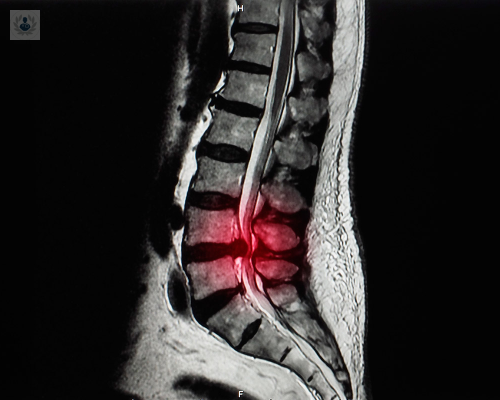

Estenosis de Canal Lumbar: causas, síntomas y tratamiento

Es una de las causas más comunes de dolor lumbar y dificultad para caminar en adultos mayores de 60 años, aunque puede presentarse antes dependiendo de factores anatómicos y degenerativos

La Estenosis de Canal Lumbar es un estrechamiento del canal raquídeo que ejerce presión sobre la parte baja de la columna espinal.

La Estenosis de Canal se refiere a la pérdida del diámetro del canal espinal o de los agujeros vertebrales por los que salen los nervios provocando que los elementos nerviosos queden comprimidos y con poco riego sanguíneo

Estenosis del Canal Lumbar y Hernia Discal: tratamientos con altos niveles de eficacia

La Estenosis de Canal como la Hernia Discal son padecimientos que muy pocas personas podrán evitar, sin embargo, existen tratamientos que pueden aplicarse a ambos padecimientos con niveles muy altos de éxito